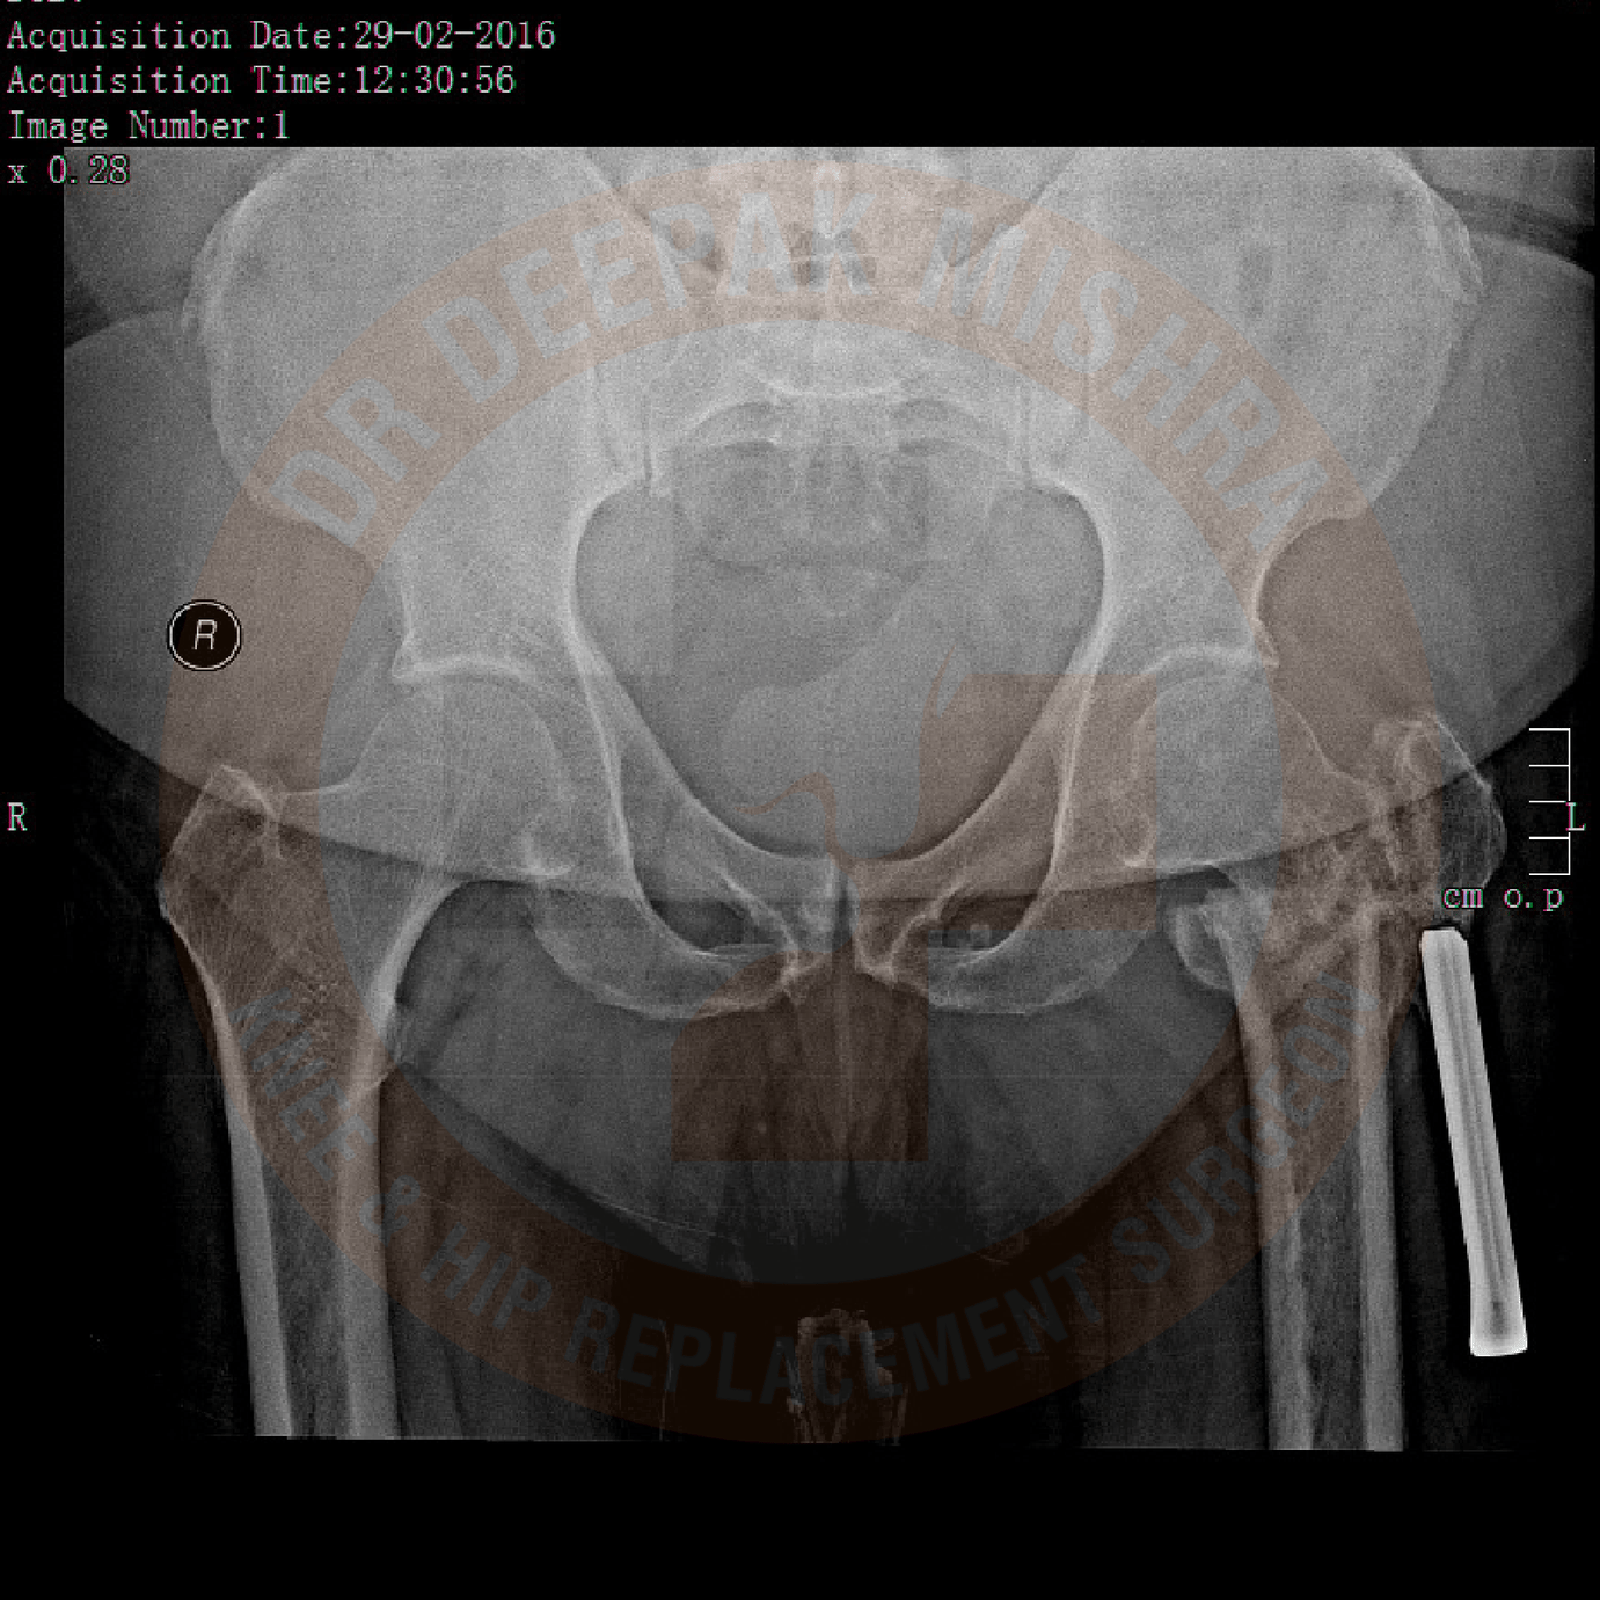

Patients with hip arthritis present with pain around their hip joint and difficulty in walking. They also have difficulty in sitting on the floor or squatting. Few patients present with complaints of not able to perform marital obligations. Detail history is taken to ascertain the underlying cause. Proper examination is performed to assess movements in the affected hip joint. Radiological and blood investigations are performed as per the requirements. MRI and CT scan (with 3D reconstruction) provided the detailed anatomical extent of disease and any associated loss of bony architecture. It is important to get as much information as possible before planning treatment options.

It usually occurs due to trauma to the hip joint, avascular necrosis (lack of blood supply to ball of the femur), infections (tuberculosis/septic), childhood hip problems (congenital hip dislocation, Perthe’s disease, slipped capital femoral epiphysis, etc) and inflammatory arthritis like rheumatoid arthritis or ankylosing spondylitis.

Due to damaged hip, patients experience pain in day-to-day activities. They have difficulty in sitting crossed leg, squatting or using stairs. As disease progresses with time, the deformities appear in hip joint leading to reduced mobility and subsequently these patients become bedridden. Increasing deformity also produces changes in spine and knee joints, if not treated on time. Few patients presents with complaints of not able to perform marital obligations.